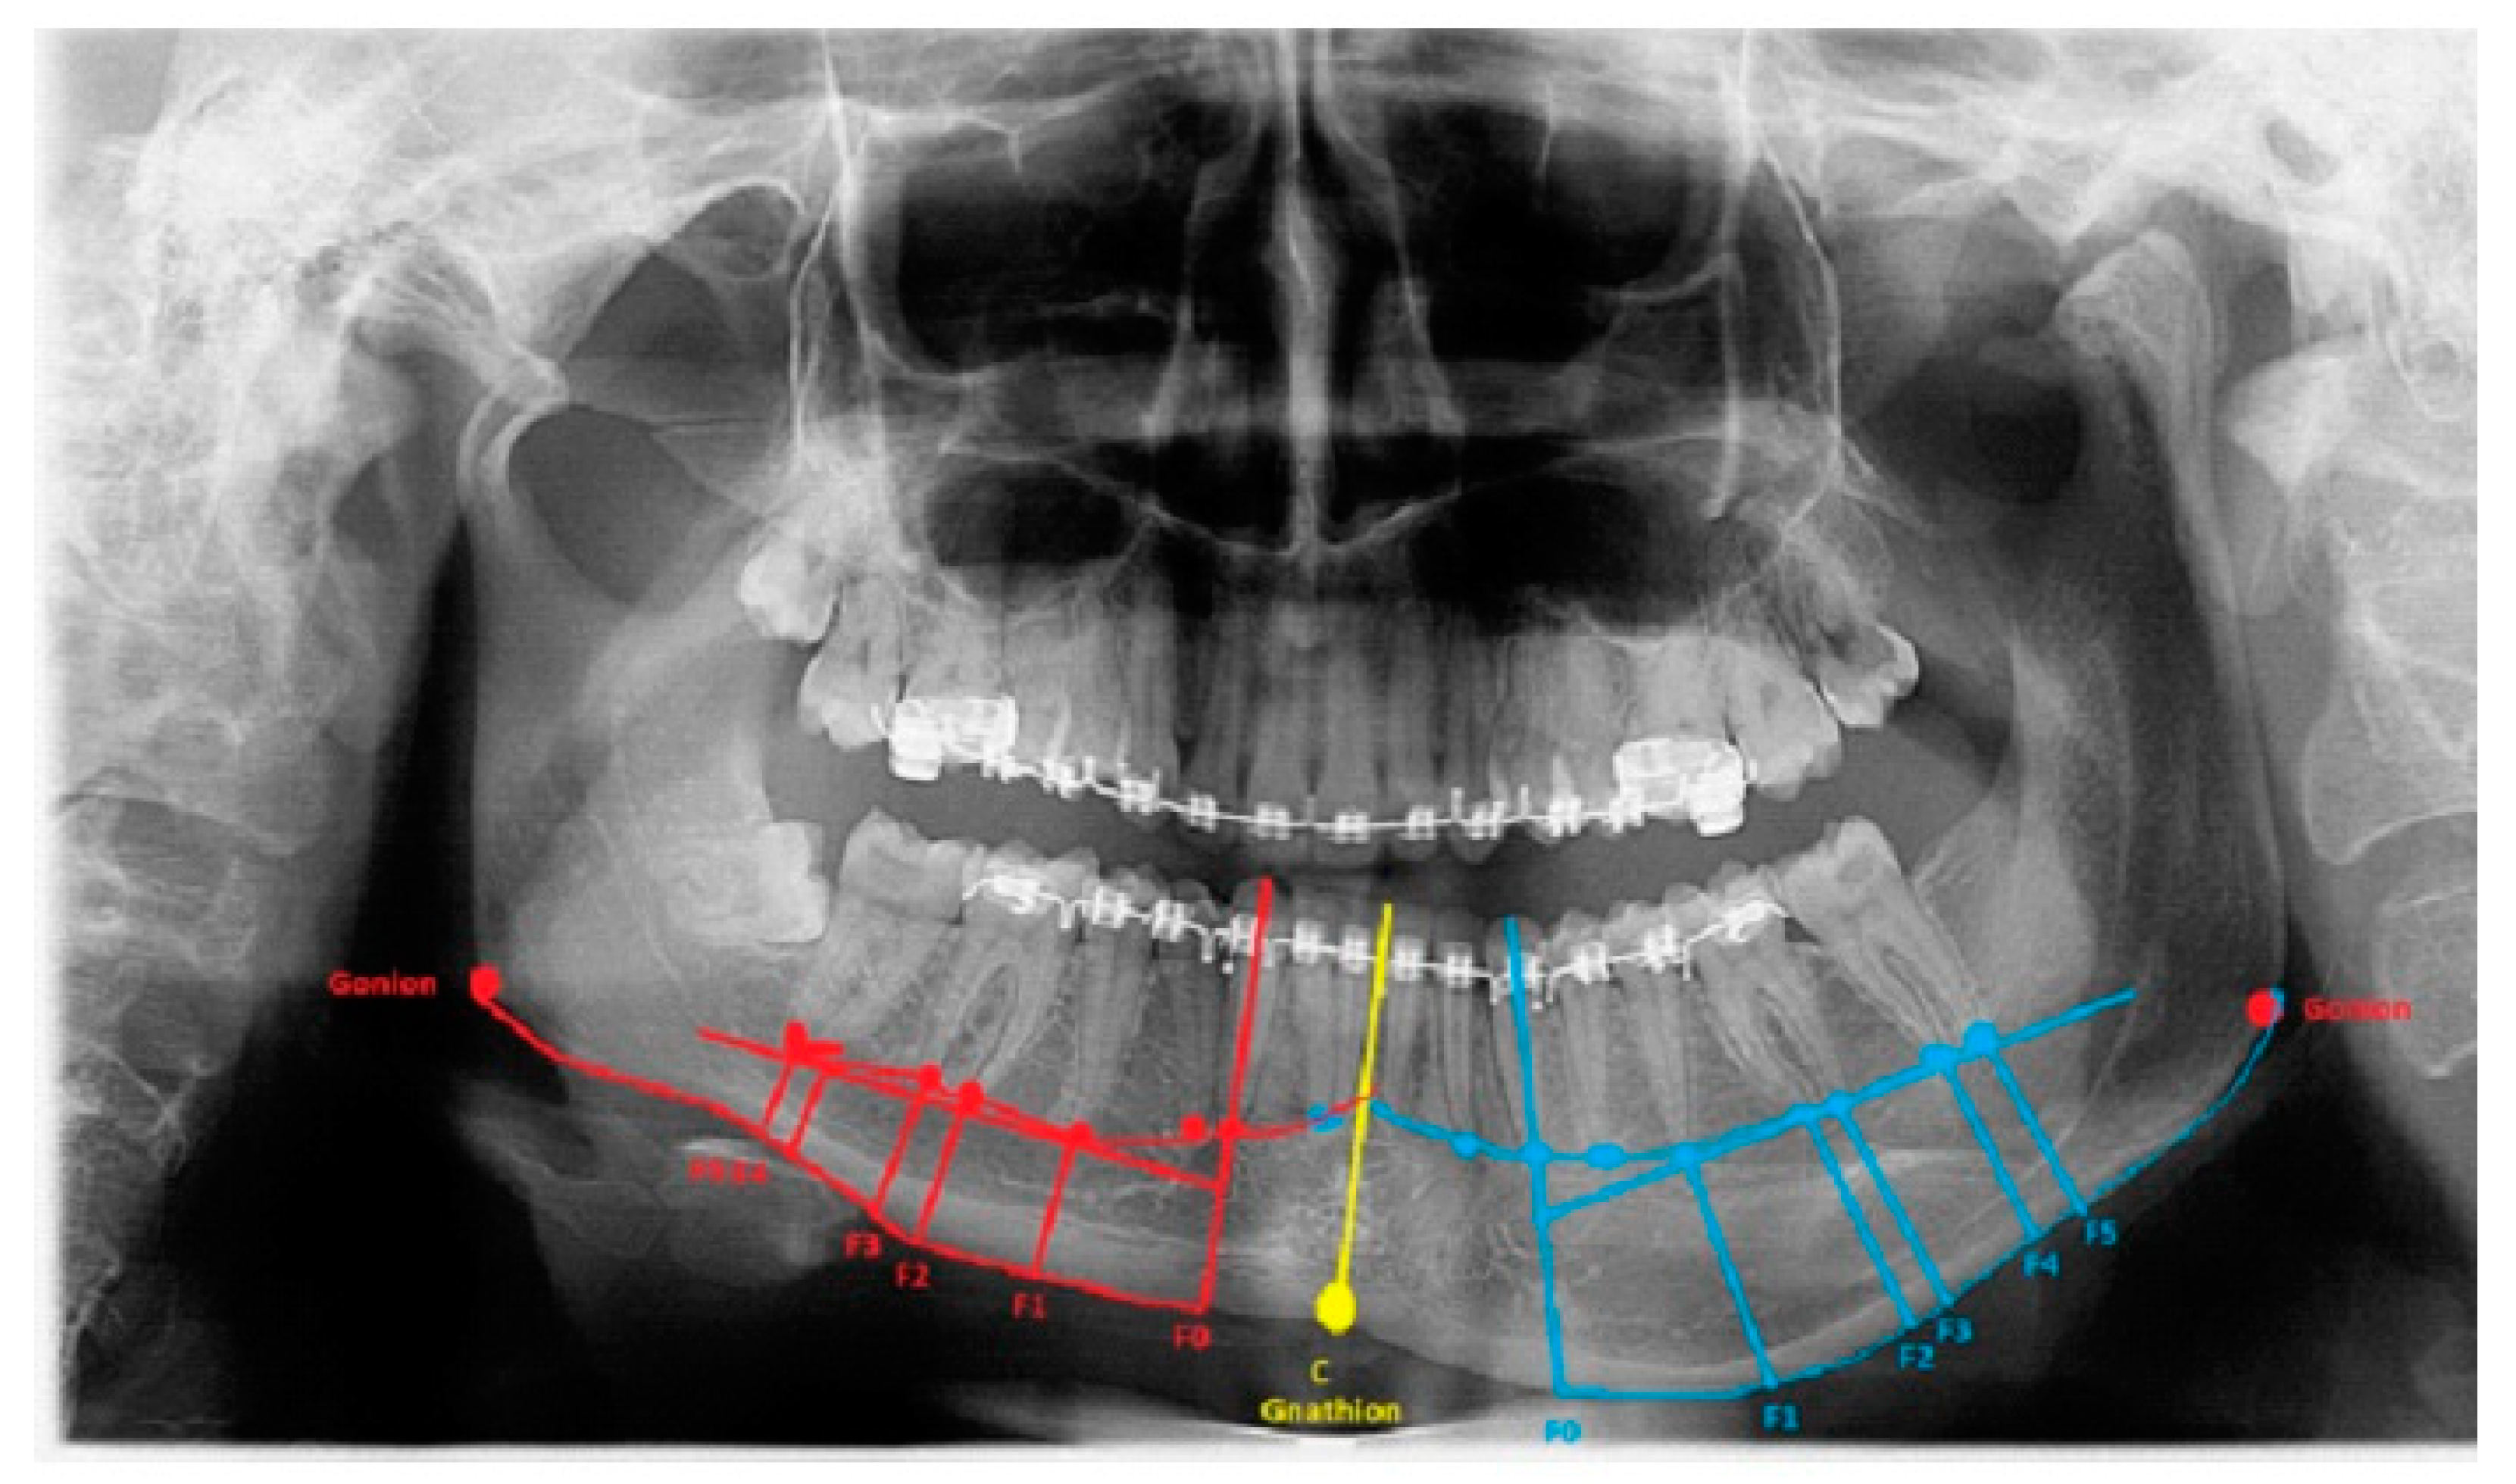

The degree of asymmetry and bone overgrowth varies in each case individually (Figure 2). A classic panoramic radiograph is sufficient to plan the scope of surgery, but because of the natural object enlargement in size by about 15–25%, any detailed measurements are troublesome. Despite this magnification, panoramic visualization enables good estimation of the degree of oversized mandibular bone, which can later be accurately measured on CT/LDCT radiographs. The authors present their proposal for approaches, the usage of which depends significantly on the anatomical-radiological distances (ARD) and proportions. All are based on the six most commonly found situations in CT/CBCT-RTG. Based on the following anatomical-topographical measurements, a protocol for surgical intervention was prepared. Perhaps the presented method of bone measurements will be a valuable study for future surgeries as condylar hyperplasia-related treatment remains without any particular guidelines and remains exceedingly individual. The detailed proposition of approaches based on the author’s proposal and own used anatomical indexes are presented in Table 2. After a detailed radiological data analysis on the RTG/panoramic and lateral cephalogram or LDCT/CT, the following anatomical-radiological proportions should be included for surgical planning:

Figure 2.

Severe form of condylar hyperplasia.

3.2. Gonial Angle

The length between Go-Gn/Go-Gn and the vertical bone volume relation decreases the bone height on the opposite healthy side—the critical point of this technique is the distance between the Go-Go/Go-Gn position and the value of the F0-C bone index. In this case, approach 1C can be used with or without corrective angulotomy/anguloplasty, which reduces the angled volume on the affected side in vertical and horizontal dimensions. If both Go (Right) and Go (Left) are situated on the same horizontal line, no major surgery should be planned, unless performing a condylectomy might relocate the Go point on the affected side to a higher position afterward. Therefore, careful planning in the horizontal plane and the F5: Go measurement can help estimate whether any additional mandibular angle surgery should be planned (Figure 1 and Figure 2; Table 1). This was used in some of the authors’ cases where there was no maxillary bite-plane deviation, and no chin bone asymmetry was present.

The authors conclude that a very severe mandibular overgrowth with increased chin involvement should be a mandatory indication for the classic Ferguson approach with a surgical reduction in the mandibular angle on the affected side [7,13]. The main reason for this is the increased distance and height of the F0:F1 and F0:C:F0 values in this study (Figure 1). The authors fully agree with Ferguson’s approach, which is confirmed in the author’s measurements based on the suggested ARP: IM values and the distances between reference points in the presented study radiographs. Two different cases of one-sided mandibular overgrowths in hemimandibular hyperplasia are drawn and explained in Figure 2.